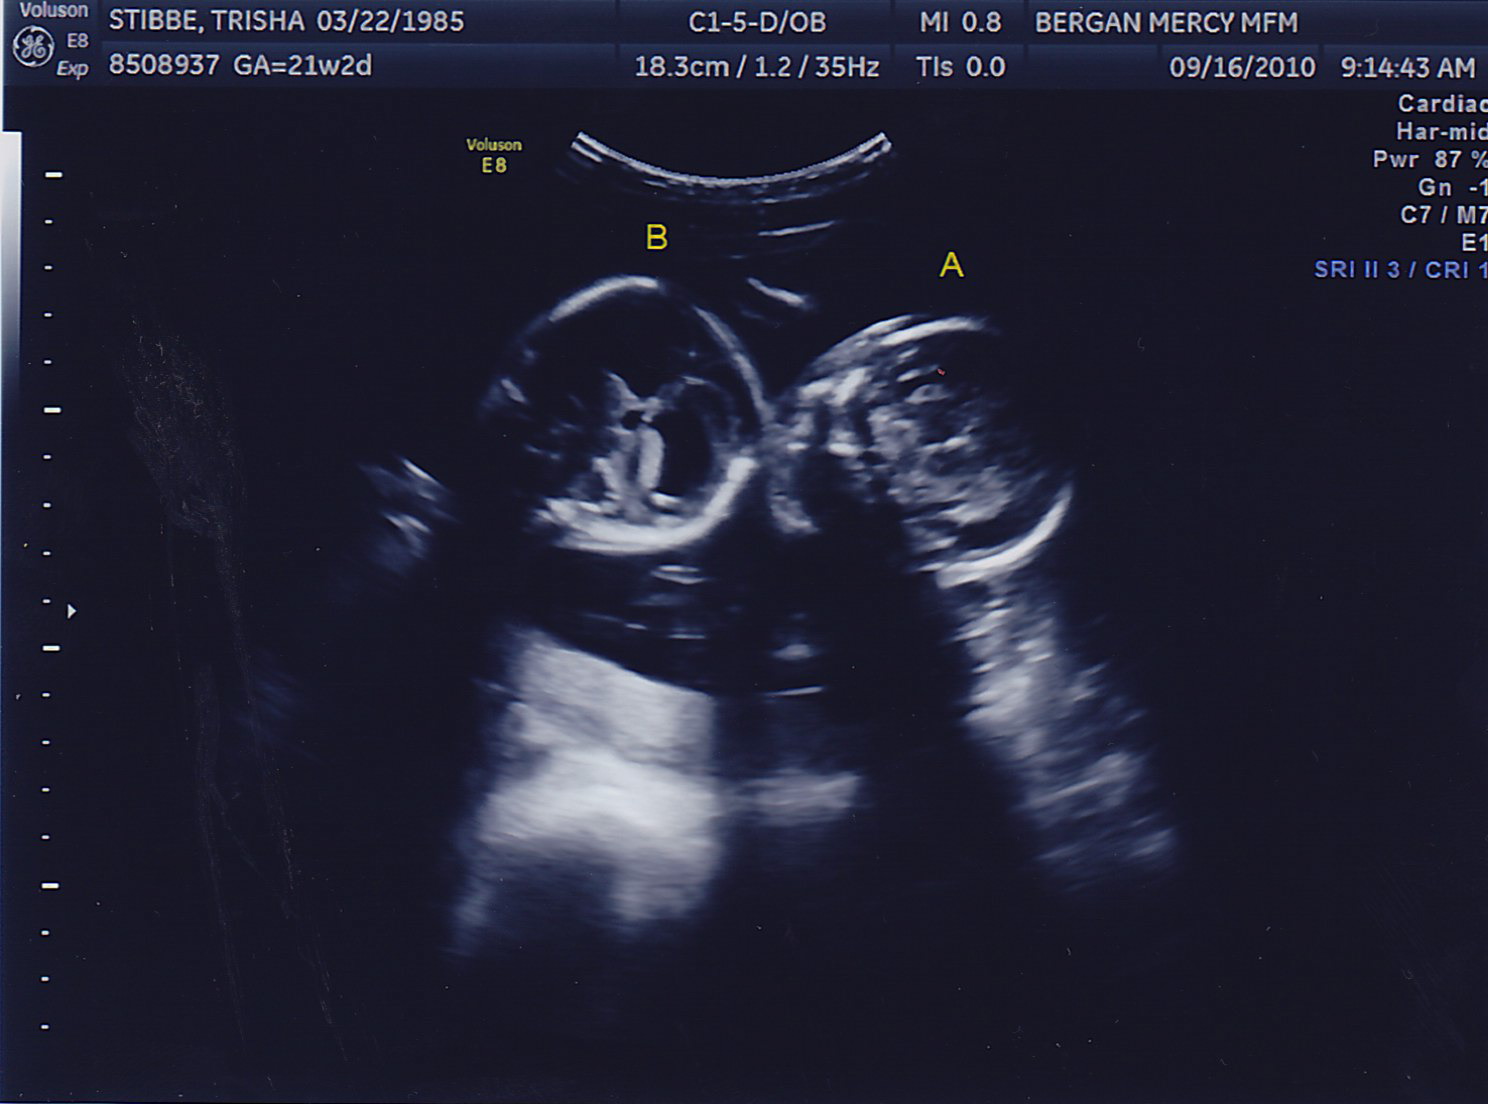

Another successful appointment! Both boys gained weight, we could see the bladder on Baby B (something the doctor needs to keep a close eye on) and the fluid levels in both looked great. No amnio therapy for Mommy today! Here are some more pictures of the little peanuts, who were called “photogenic” by the sonographer today <– very proud Mom-moment 🙂